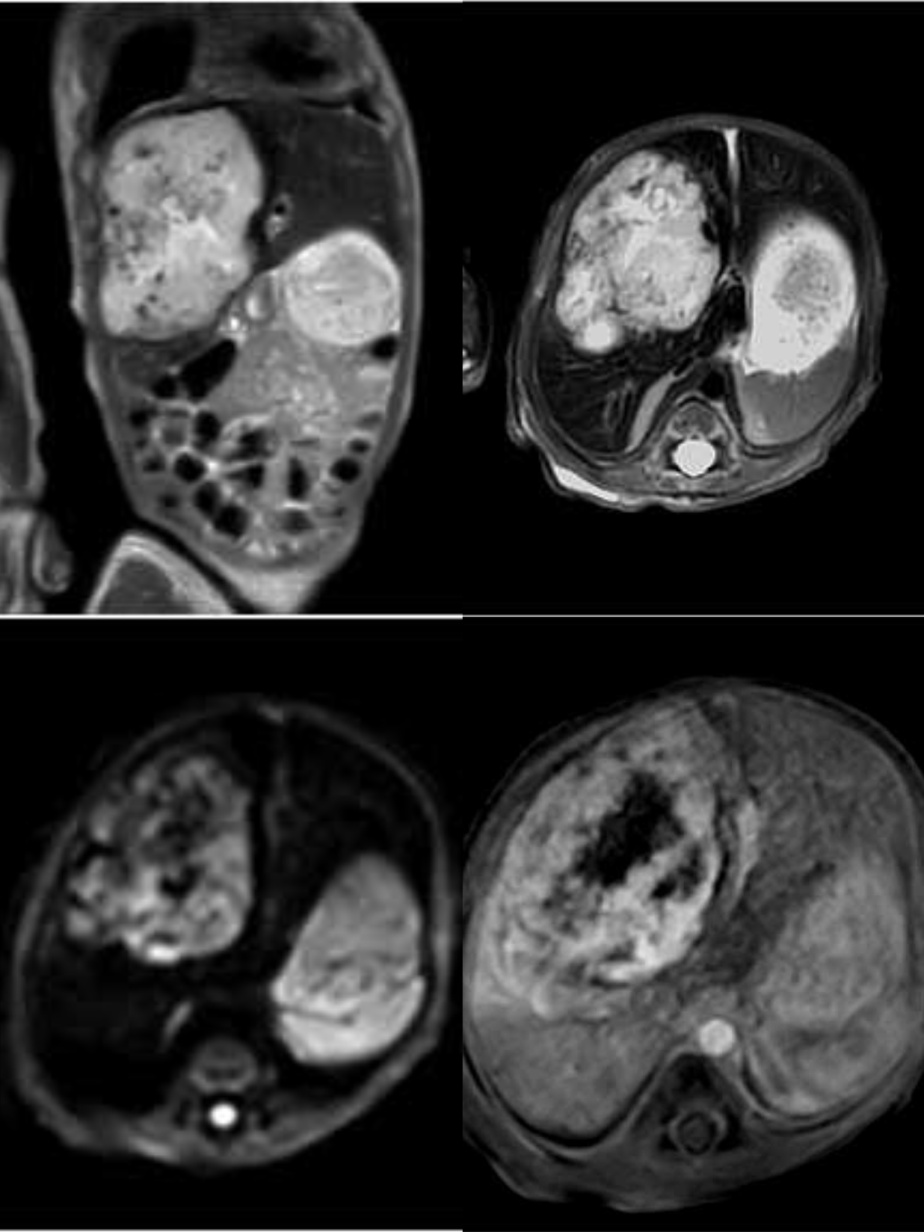

2024年4月29日中午,磁共振室完成了一例出生仅4天、体重不足2.6千克的新生儿上腹部MRI平扫、DWI功能成像以及动态增强扫描,创下目前三级片

MRI增强扫描患者年龄最小、体重最轻的新记录。

4月29日中午,在新生儿科卢红茹副主任医师和张莉莉主管护师全程保驾护航和雷晓燕主任悉心指导下,张鑫技师长和李娟主管护师、程苗技师在做好前期充分准备工作后,三人默契配合,选择更贴近患儿身体的膝关节线圈,并调整检查序列,克服患儿血管纤细、不时哭闹、无法运用呼吸触发和屏气等重重困难的情况下,仅用时二十分钟,顺利完成了上腹部MRI平扫、动态增强扫描及功能成像(DWI)检查,并获得满意的图像。